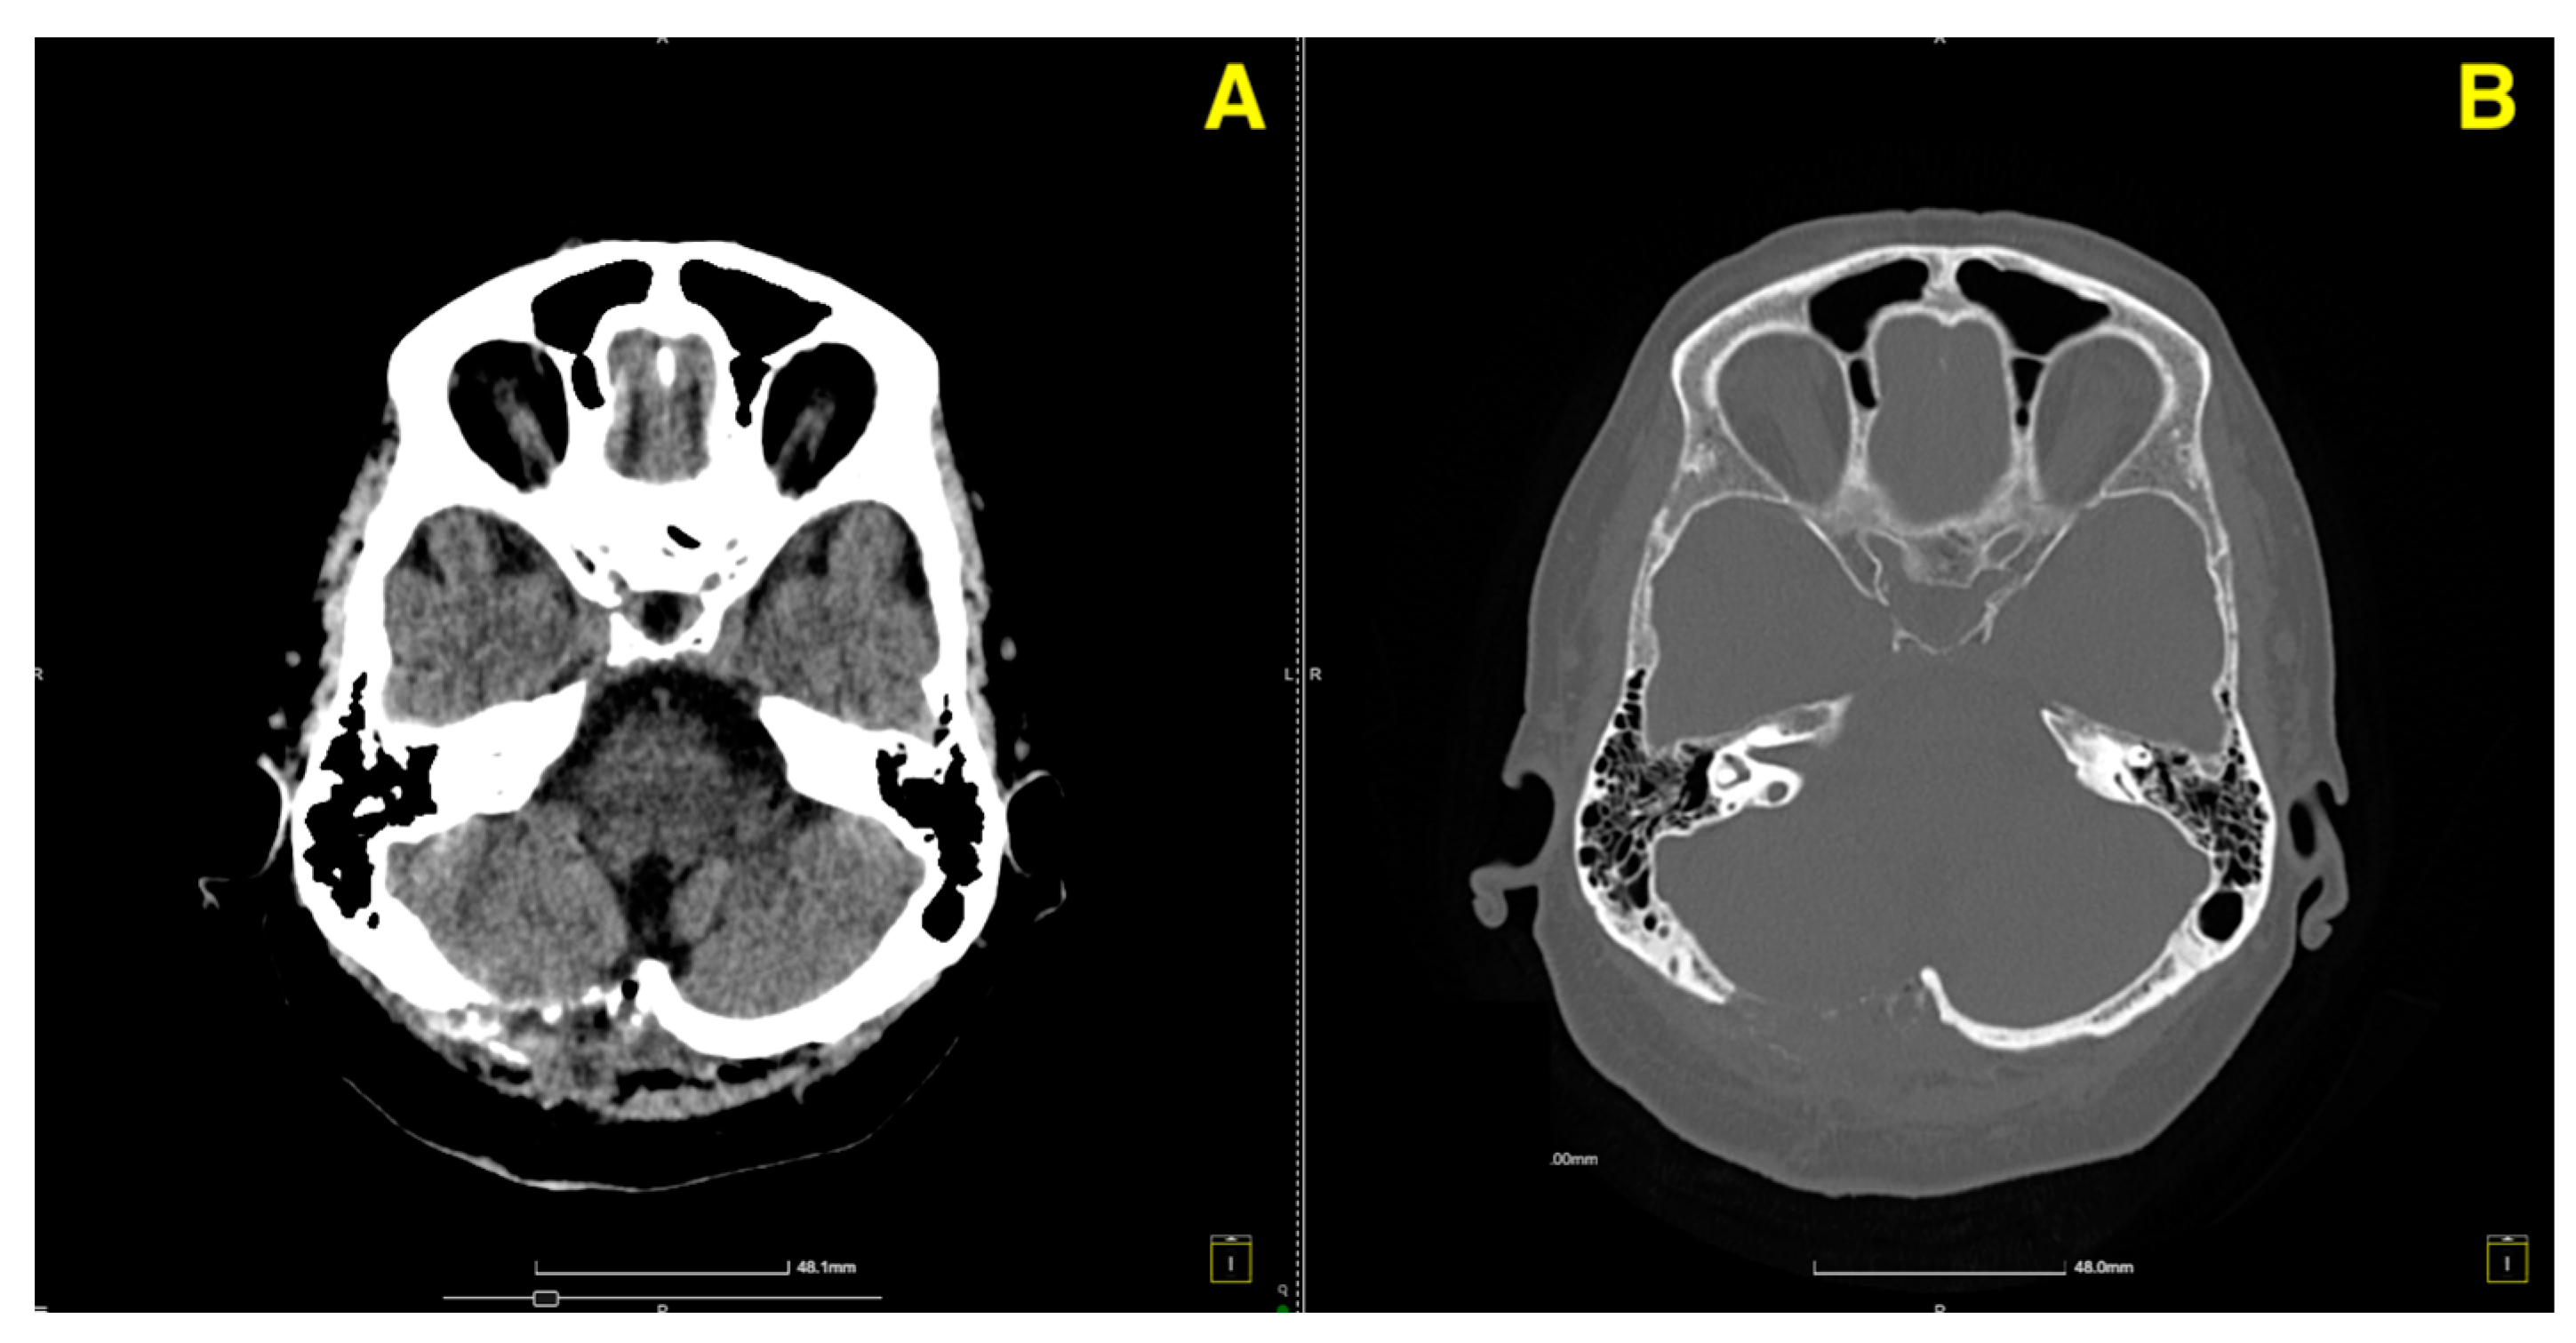

The two-month postoperative CT scan (Figure 4) confirmed excellent surgical outcomes. The right cerebellar hemisphere, where the cavernoma had been resected, demonstrated normal postoperative changes, with no signs of residual cavernous malformation or new lesions. The surgical cavity appeared stable, and no signs of hemorrhage or fluid collection were noted.

Clinically, the patient continued to demonstrate full recovery, with no neurological deficits. Coordination tests remained normal, and there was no recurrence of her vertigo or gait instability. Given these findings, the patient was discharged from regular follow-up, with instructions for routine imaging in the future as part of long-term surveillance. At the 1-year follow-up, a control CT scan (Figure 5) was performed to assess the long-term stability of the surgical site and ensure that no delayed complications had arisen.

The patient remained asymptomatic and fully functional at the 1-year mark, with no recurrence of vertiginous symptoms or neurological deficits. Based on these findings, the patient was advised to continue with routine imaging as part of long-term surveillance, but no further immediate follow-up was deemed necessary given the stable postoperative course.

Figure 4. Two-month follow-up post-op CT scan. (A): Axial CT image of the right cerebellar hemisphere shows normal postoperative changes (red arrows) in the area of the cavernoma resection, with no residual cavernous malformation, new lesions, or signs of fluid collection or hemorrhage. (B): Coronal CT image further confirms the stability of the surgical cavity (red arrow), with no evidence of hemorrhage, recurrent lesions, or abnormal findings in the surrounding structures.

Figure 5. One-year follow-up control CT. (A): Axial CT image displays the postoperative region in the right cerebellar hemisphere, showing well-preserved stability with no residual cavernoma or evidence of delayed complications, such as hemorrhage or fluid accumulation. The surrounding cerebellar tissue remains intact and unaffected. (B): Coronal CT image highlights the absence of recurrent lesions or structural abnormalities at the surgical site. The cavity remains unchanged, reflecting long-term postoperative success without any signs of new pathological findings.